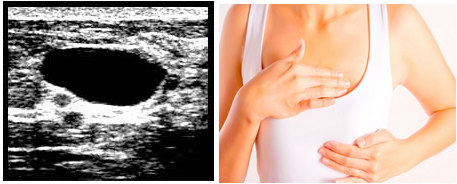

Похудение и киста молочной железы - фото презентация